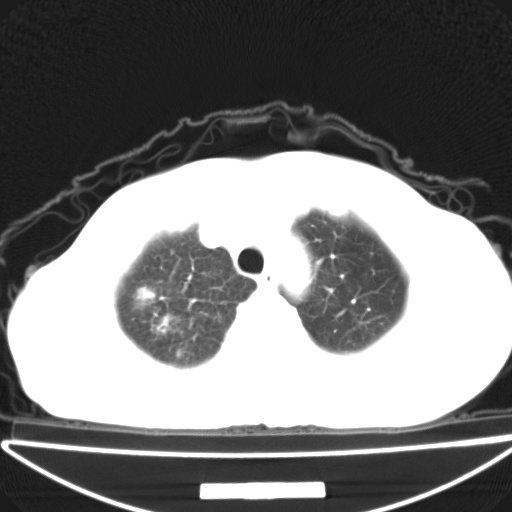

以下是引用jsgdoctor在2008-11-6 22:12:00的发言:[br]右主支气管壁明显增厚,管腔狭窄.考虑为右侧中央型肺癌伴阻塞性炎症\\肺脓肿.

以下是引用zjzjr在2008-11-6 20:25:00的发言:[br]中心型肺ca,合并阻塞性肺炎

以下是引用zsl6918在2008-11-6 19:43:00的发言:[br]右侧中心性肺癌(鳞癌)